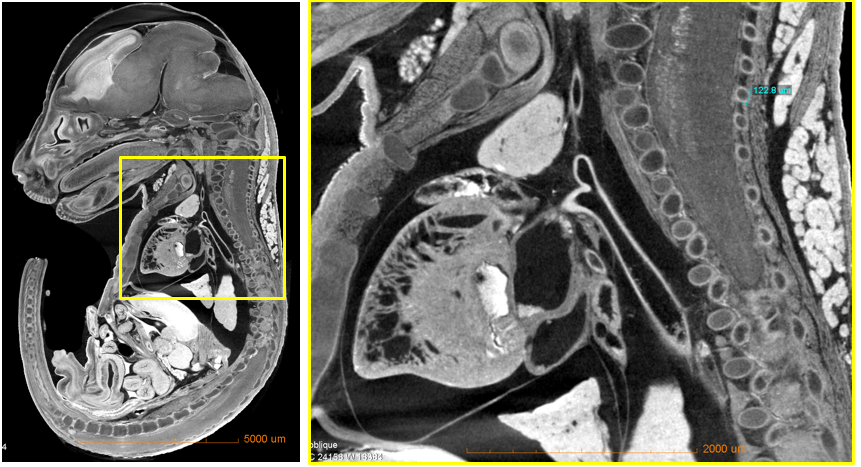

三维无损成像:可对生物、材料等实验材料进行三维无损成像,图为6.5 um体素分辨率扫描的小鼠胚胎。

(a)图为使用6.5um体素分辨率拍摄的2D切片(b)图为对感兴趣位置进行放大拍摄,可清晰看见脊椎以及内脏结构。